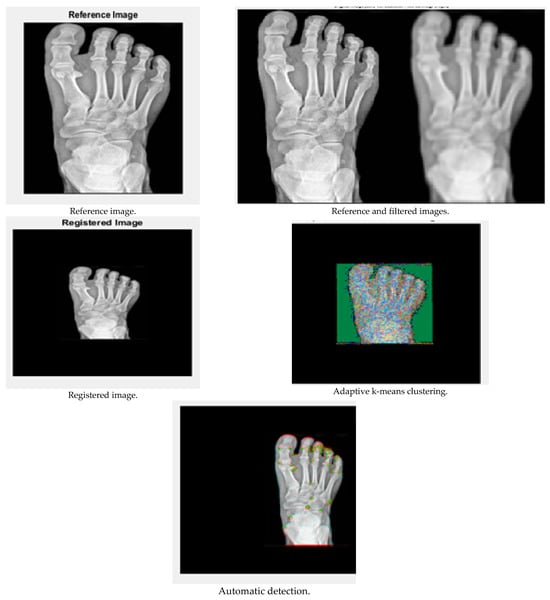

The performance of the results is demonstrated in this Results and Discussion section. The input X-ray images were taken from the website kaggle, and the results were obtained using MATLAB R2019a. The results are shown in Figure 3 and Figure 4:

Figure 3.

Performance analysis of image 1.